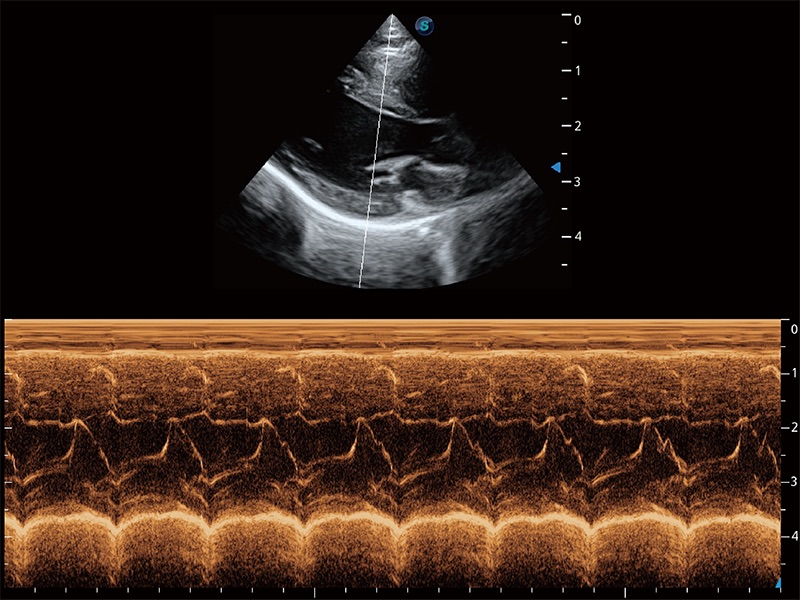

得心应手 心脏解决方案

ProPet 80 配备了丰富的心脏探头群、先进的成像技术和专业的心脏测量工具,可帮助动物医生为不同体型和生理结构的动物提供心脏和心肌功能的全面评估。

• AMM 解剖M型

通过360度任意调节3条M型取样线,在同一心动周期上观察心脏不同位置的运动曲线,得到准确的心功能测量数据,有效评估心肌运动及左心室功能。

(猫)二尖瓣M型